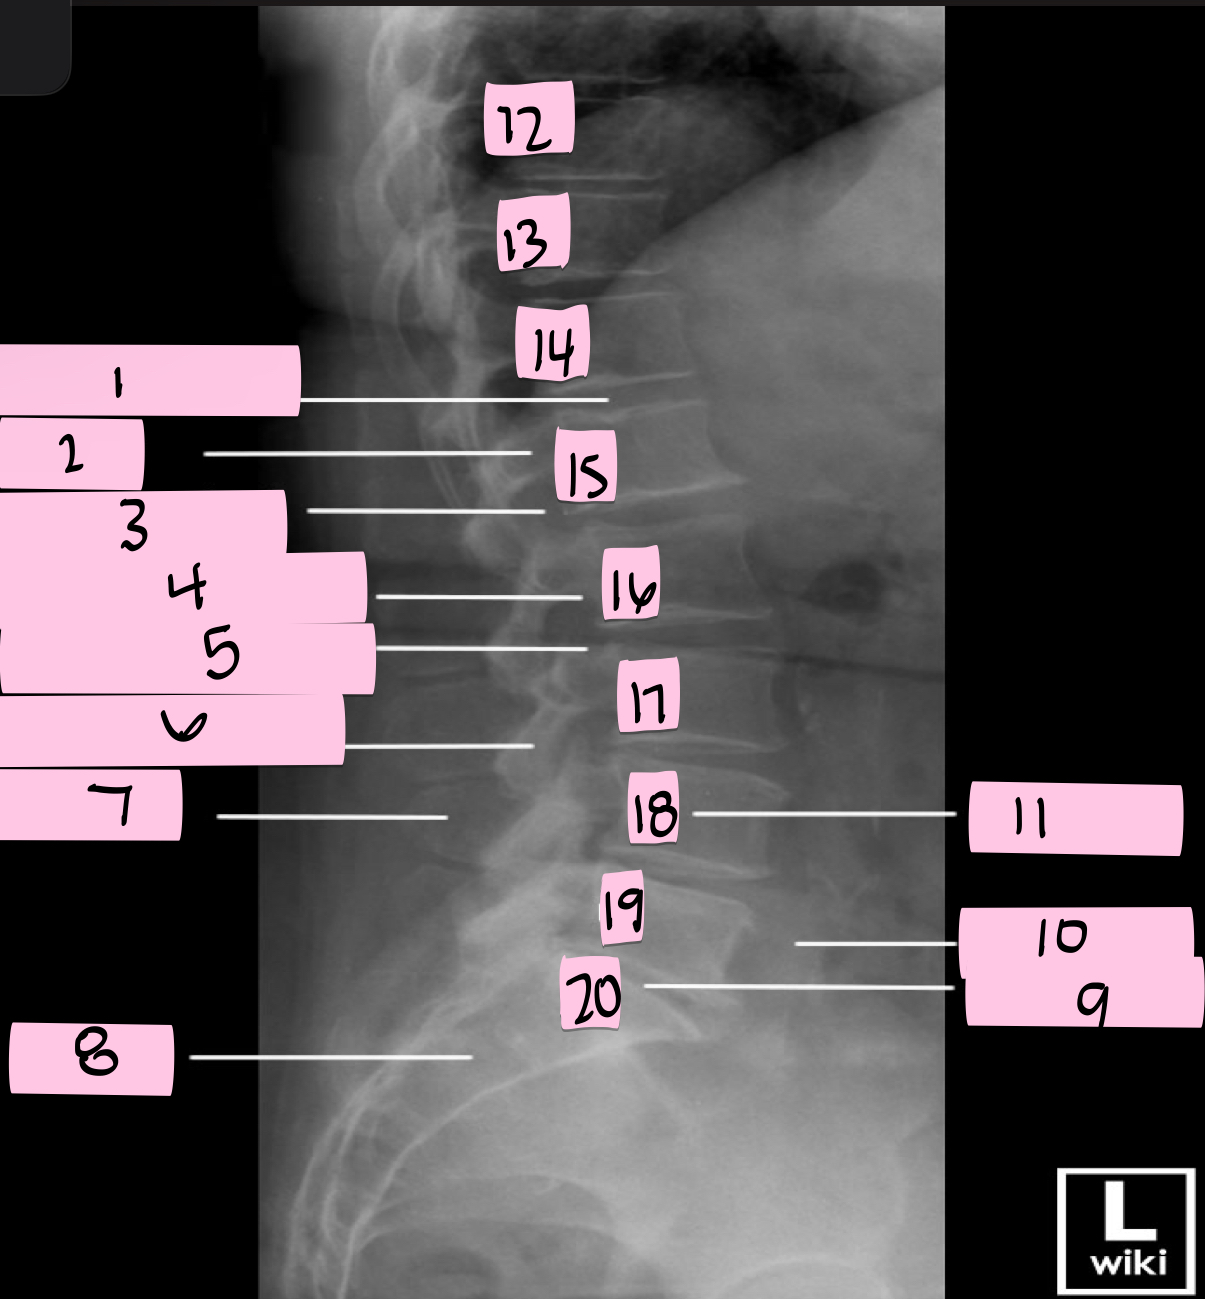

What is 1 pointing to?

Intervertebral disk

What is 2 pointing to?

Pedicle

What is 3 pointing to?

Intervertebral foramen

What is 4 pointing to?

Inferior vertebral notch

What is 5 pointing to?

Superior vertebral notch

What is 6 pointing to?

Inferior articular process

What is 7 pointing to?

Spinous process

What is 8 pointing to?

Sacrum

What is 9 pointing to?

L5 S1 joint

What is 10 pointing to?

Iliac crest

What is 11 pointing to?

Vertebral body (L4)

What is 12 pointing to?

T10

What is 13 pointing to?

T11

What is 14 pointing to?

T12

What is 15 pointing to?

L1

What is 16 pointing to?

L2

What is 17 pointing to?

L3

What is 18 pointing to?

L4

What is 19 pointing to?

L5

What is 20 pointing to?

S1